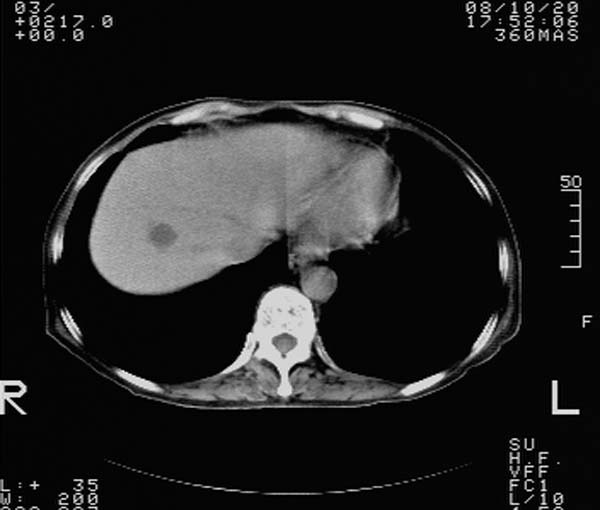

f,67y。反复右上腹痛。余无异常。

前五幅未服造影剂。后面图像有上传重复的。请战友们发表意见。

胆囊结石、胆囊癌伴邻近脏器受侵,不除外黄色肉芽肿性胆囊炎,建议增强扫描。肝多发囊性占位性病变,囊肿或囊性转移。

胆囊内结石,胆囊壁不规则增厚,胆囊胃窦区解剖结构欠清晰,楼主提示为少见病,考虑bouveret综合征?黄色肉芽肿性胆囊炎?肝内多发低密度占位,建议增强或b超